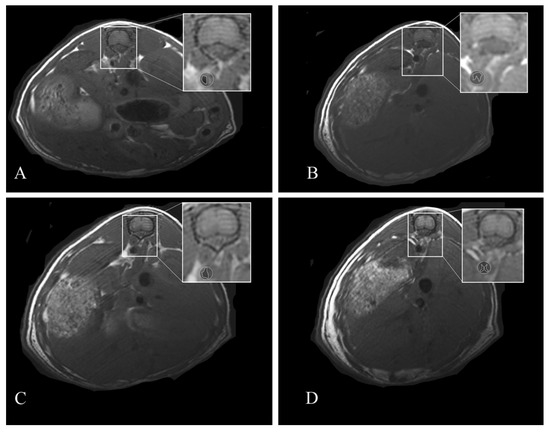

2.4. Magnetic Resonance Imaging

3.2. HFUS and MRI Monitoring

3.3. Atherosclerotic Plaque Development